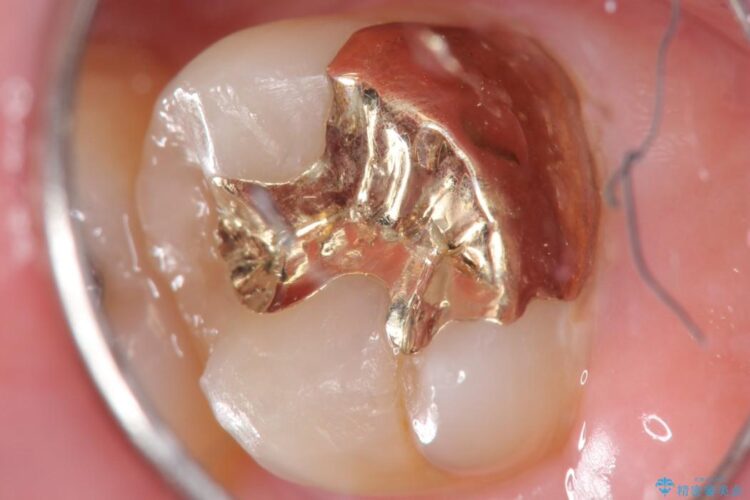

今回は一番奥の歯という位置と、噛み合わせ、清掃状態を加味して適合の高く長持ちするゴールドインレーにて治療することとしました。

ゴールドインレー

ゴールドインレーはセラミックより強度高く、使用される金合金や白金加金は汚れの付きにくいという特徴を持っており、耐用年数が長いことが特徴としてあります。特に奥歯など強く力が欠けられる箇所に適しています。